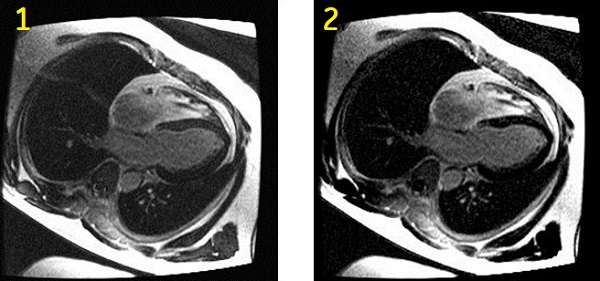

Figure 2. Heart comparison images

Table 2. Image legend Number Description 1 Magnitude myocardial delayed enhancement image. Shorter than optimal TI time selection results in incomplete myocardial suppression and grey-like myocardial signal. 2 Phase-sensitive myocardial delayed enhancement image. Improved myocardial suppression (darker myocardial signal) is achieved despite shorter than optimal TI time selection. - Setup the patient. For details, see: